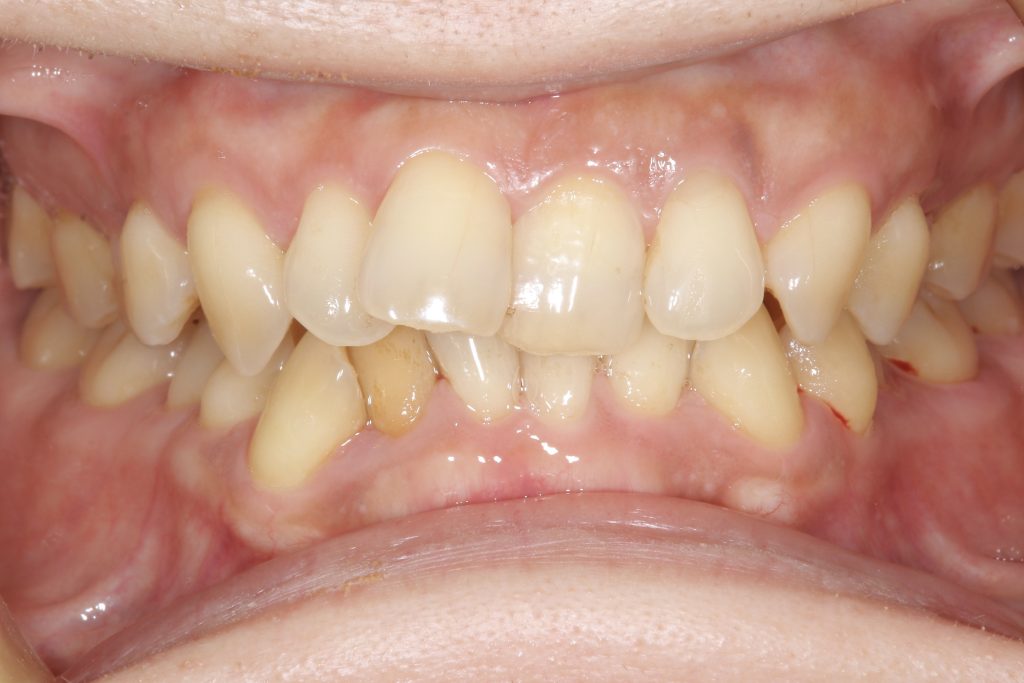

「人前で笑えないのがずっとコンプレックスでした。受け口の歯並びは長年気になっていたけれど、もう40代だし、今さら治療するのもなぁと…」

受け口の状態により、上の歯が内側に入り込み、反対の噛み合わせになっている部分が見られました。見た目の問題だけでなく、噛み合わせのバランスにも影響を与えていました。

- 前歯部交叉咬合を伴う不正咬合

- ゴムメタルワイヤー矯正

- 2024年9月6日(10ヶ月)